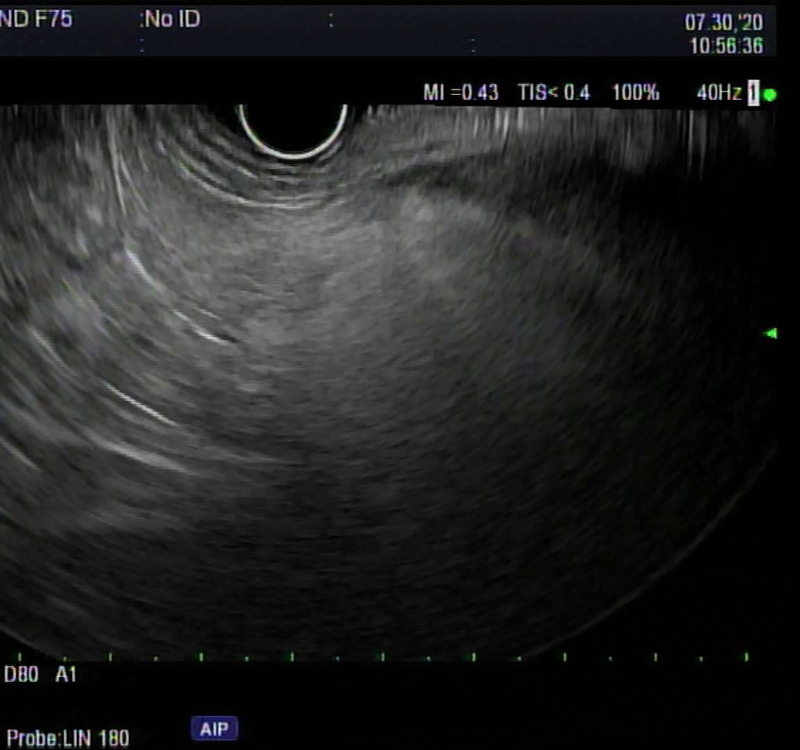

背景和目的:脂肪性胰腺(FP),传统上被认为是一种良性发现,最近由于越来越多的证据将其与各种疾病状态联系起来,包括胰腺癌(PC)的风险增加,因此一直受到密切关注。方法:回顾性研究2007年8月至2023年10月在单一机构接受EUS的患者,由一名具有25年以上经验的超声医师进行。针对在EUS期间确诊为FP的个体,我们将这些发现与EUS前后3个月或1年内进行的计算机断层扫描/磁共振成像(CT/MRI)的相应发现进行了比较。结果:纳入91例患者,并在EUS检查中确定为FP。高危患者中最常见的适应症是PC筛查(35.16%)。进行EUS检查时,65.93%的患者体重指数(BMI)≥30,63.73%的患者患有高血压,32.96%的患者患有2型糖尿病。在91例患者中,70例在EUS检查后3个月内进行了CT或MRI检查,仅有15例(21.43%)在影像学上报告了FP。91例患者1年内均行CT或MRI检查,影像学报告FP仅16例(17.58%)。结论:尽管EUS发现FP,但只有21.43%的患者在3个月内在CT/MRI上发现FP,这表明CT/MRI在识别FP方面的准确性低于EUS,或者在现实环境中可能漏报FP,即使在三级医疗中心也是如此。考虑到FP作为几种重要疾病和促进胰腺癌发生途径的潜在前体的作用,这种报道的差异值得注意。

Background and objectives: Fatty pancreas (FP), traditionally perceived as a benign finding, has been undergoing scrutiny lately due to growing evidence linking it to various disease states, including increased risk for pancreatic cancer (PC).

Methods: A retrospective study of patients who underwent EUS at a single institution from August 2007 to October 2023, conducted by one endosonographer with more than 25 years of experience. Focusing on individuals identified with FP during EUS, we compared these findings with corresponding findings on computed tomography/magnetic resonance imaging (CT/MRI) conducted within 3 months or 1 year prior to or following EUS.

Results: Ninety-one patients were included and identified as having FP on their EUS exams. The most common indication for EUS was PC screening in high-risk patients (35.16%). At the time of conducting EUS, 65.93% of patients had a body mass index (BMI) ≥30, 63.73% had hypertension, and 32.96% had type 2 diabetes mellitus (DM). Of the 91 patients, 70 had CT or MRI done within 3 months of the EUS date, and only 15 (21.43%) had FP reported on imaging. All 91 patients had CT or MRI within 1 year, and only 16 (17.58%) had FP reported on imaging.

Conclusion: Only 21.43% of patients had FP on their CT/MRI within 3 months despite EUS findings, suggesting either lower accuracy of CT/MRI compared to EUS in identifying FP or potential underreporting in a real-world setting, even in a tertiary care center. This discrepancy in reporting is noteworthy considering FP's role as a potential precursor to several important conditions and promoting pancreatic carcinogenesis pathways.